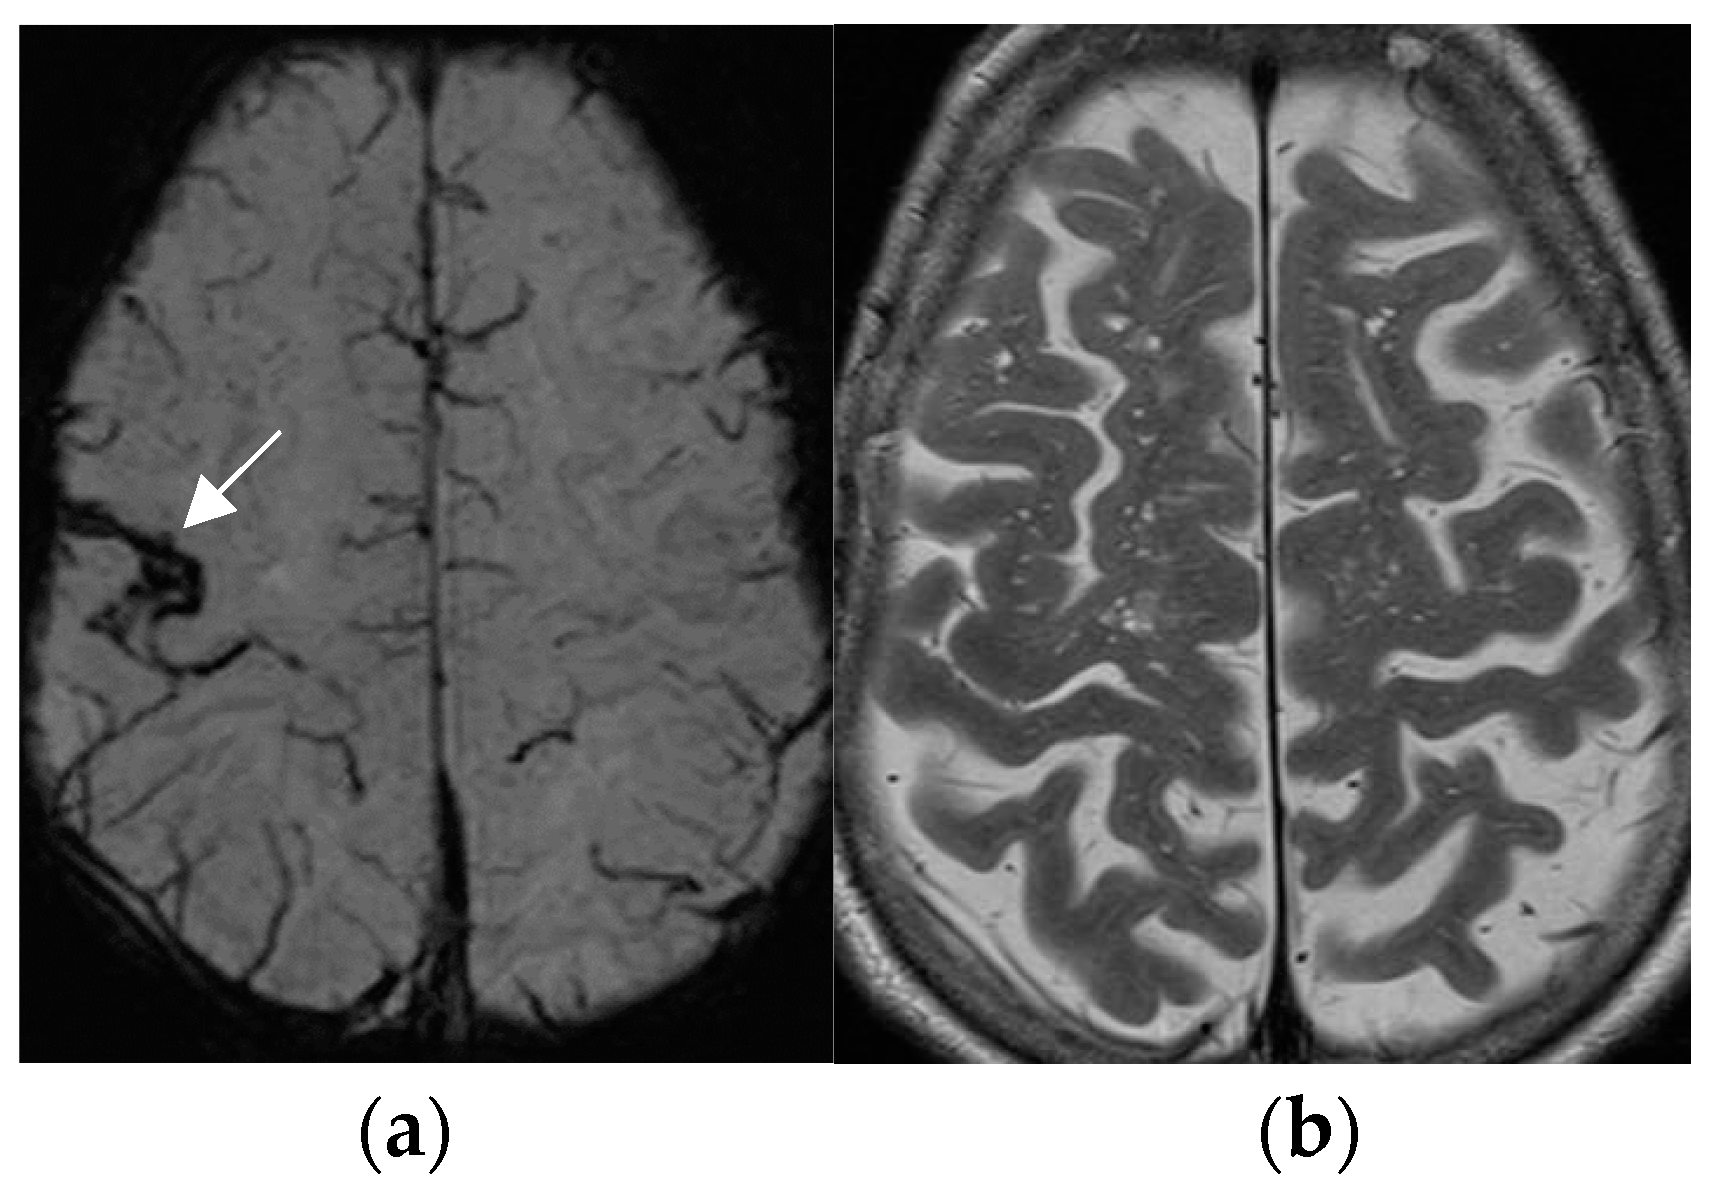

The SWI sequence depicts hemosiderin and calcification and thus renders visible cavernoma and cerebral and superficial siderosis as figureheads of cerebral amyloid angiopathy or posttraumatic or postsurgical siderosis (Figure 4).

Figure 4.

Amyloid angiopathy as evidenced by superficial siderosis within the right central sulcus on SWI sequence (arrow in (a)); invisible on the corresponding axial T2 w image (b); patient with focal seizures localized within the left hand.

Based on the SWI sequence, additional information was obtained in 13/59 (22%) of patients assessed by 1.5T MR [73].

A less-recognized feature of the SWI sequence is the paramagnetic effect of deoxyhemoglobin as a surrogate marker of vessel caliber. Pseudonarrowing of vessels may serve as a sign of regional hyperperfusion (Figure 5) and, thus, may indicate nonconvulsive status epilepticus [74,75].

Figure 5.

Non-convulsive absence status with left-sided pseudonarrowing of the mesiotemporal portion of basal vein (arrow in (a)) and hippocampal veins (arrowhead in (a)) as compared to the normal right side and mesiotemporal hyperperfusion; (CBF = cerebral blood flow image (b)) indicated by left light-green mesiotemporal hypervascularity (arrow in (b)).